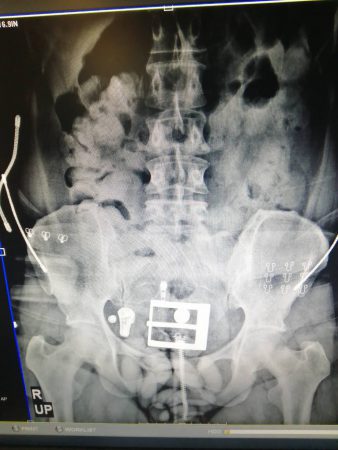

จากการปฏิบัติการร่วมกันภายใต้โครงการ “การสกัดกั้นยาเสพติดพื้นที่ท่าอากาศยาน (Airport Interdiction Task force : AITF)” อย่างต่อเนื่องส่งผลให้วันที่ 2 พฤศจิกายน 2562 สามารถสกัดกั้นการลักลอบนำยาเสพติดเข้าประเทศได้โดย จับผู้ลักลอบลำเลียงเป็นหญิงชาวเคนยา ซึ่งเดินทางมาจากประเทศแองโกลา พร้อมโคเคนนำ้หนักประมาณ 1.2 กิโลกรัม ซุกซ่อนในร่างกายด้วยวิธีการกลืนมา ที่ท่าอากาศยานสุวรรณภูมิ

*ภาพประกอบจากเคสล่าสุด (หญิงชาวเคนยา)@จจ. ป. ป. ส. # ธวัชชัย เฟื่องอนันต์ รายงาน